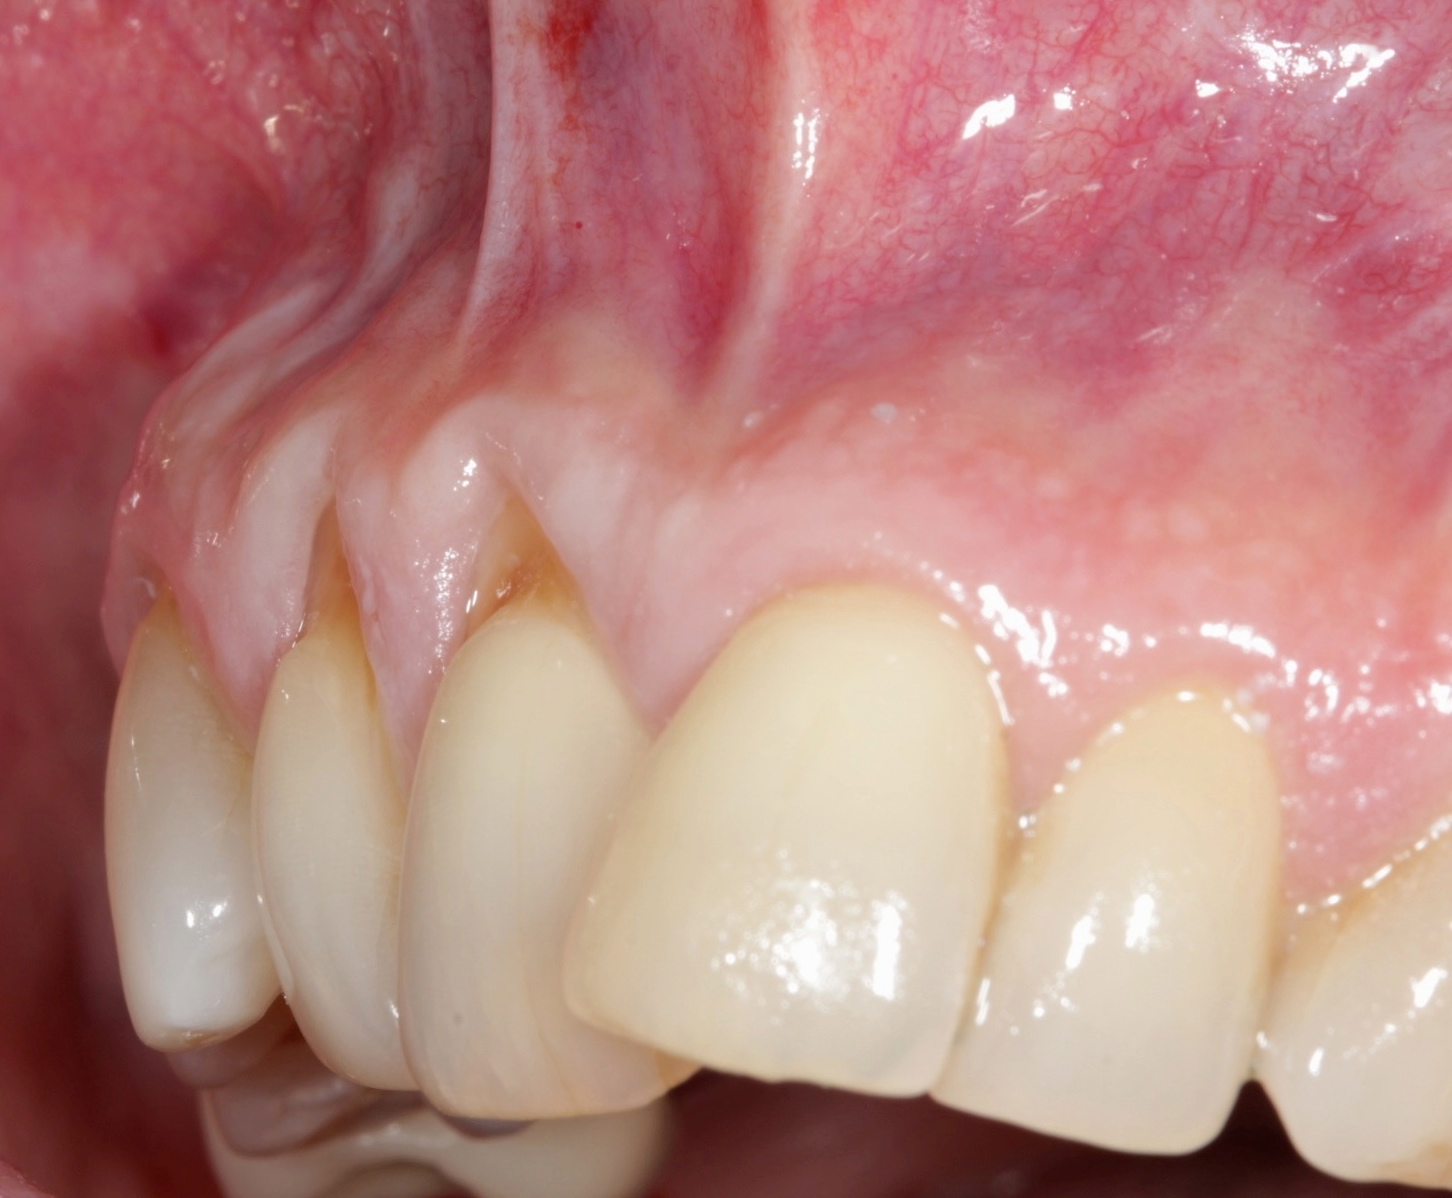

Fig 10. Cross-sectional view of the preoperative and postoperative (2 years). A three-dimensional increase of zone of keratinized and attached tissue is observed, restoring the lost attachment apparatus and correcting the gingival deformity in height and width.

Figure 10

Fig 11. Cross-sectional view of the preoperative and postoperative (2 years). A three-dimensional increase of zone of keratinized and attached tissue is observed, restoring the lost attachment apparatus and correcting the gingival deformity in height and width.

FIgure 11